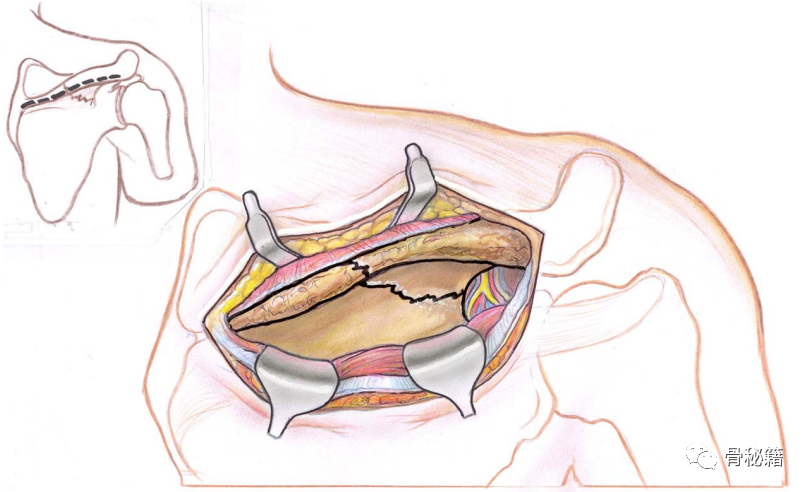

手术入路

一般选用侧卧位,沿肩胛冈下缘入路显露

注意三角肌的止点不要剥离过多

钢板可置放与肩胛冈的上缘或者下缘

避免引起皮肤的撞击

也可以采用克氏针张力带技术固定